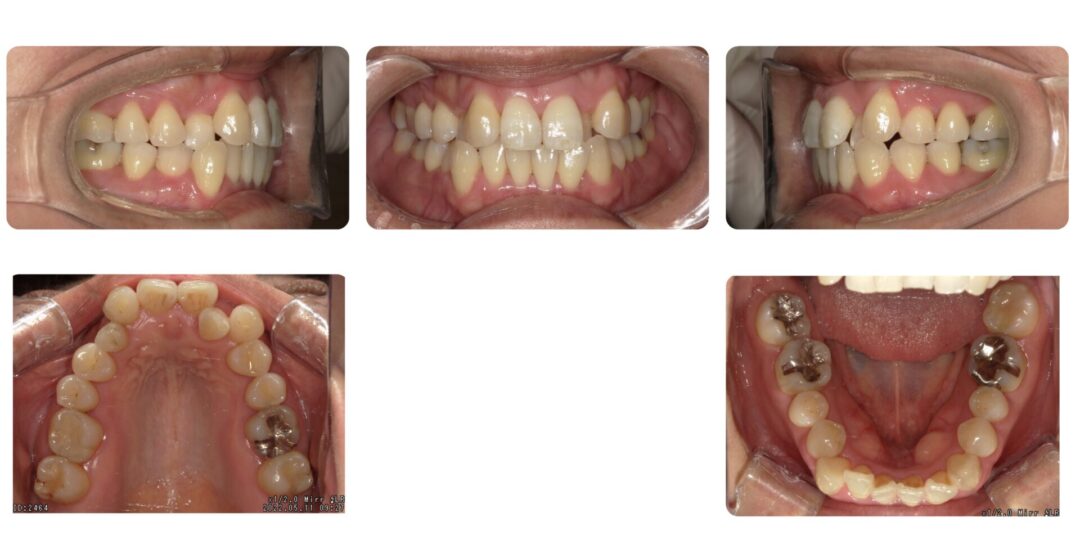

上顎左右2番反対咬合を伴う叢生|初診時46歳

矯正治療前

ご相談内容

上の前歯の歯並び、八重歯が気になる

治療内容

成人歯科矯正 非抜歯 インビザライン矯正

治療期間

2年2ヶ月

治療費用

自由診療 基本料金インビザライン矯正¥880,000(開始当時)

インビザライン矯正のための精密検査¥22,000、処置料¥5,500